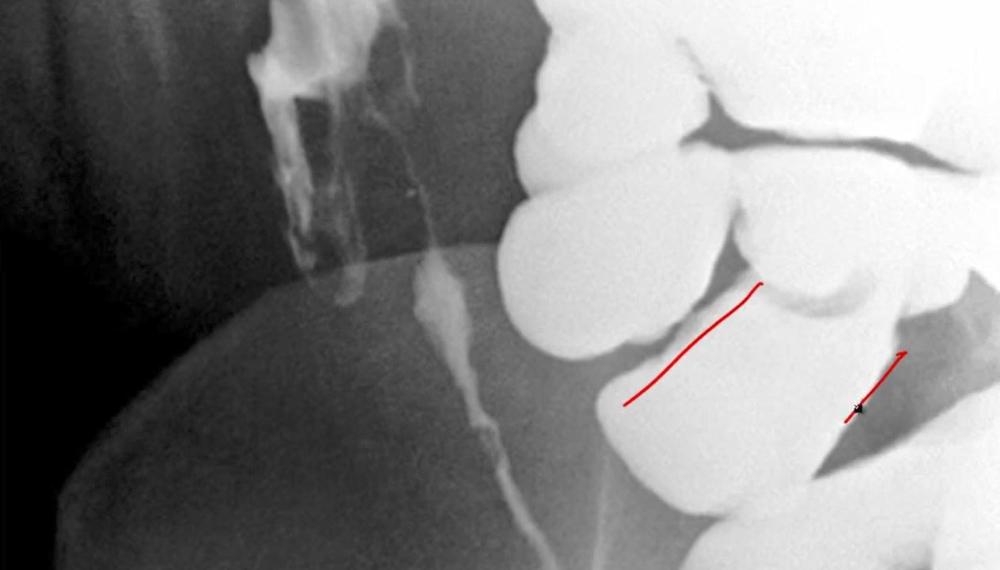

card image

what is happening here?

lead pipe sign- loss of haustra, UC